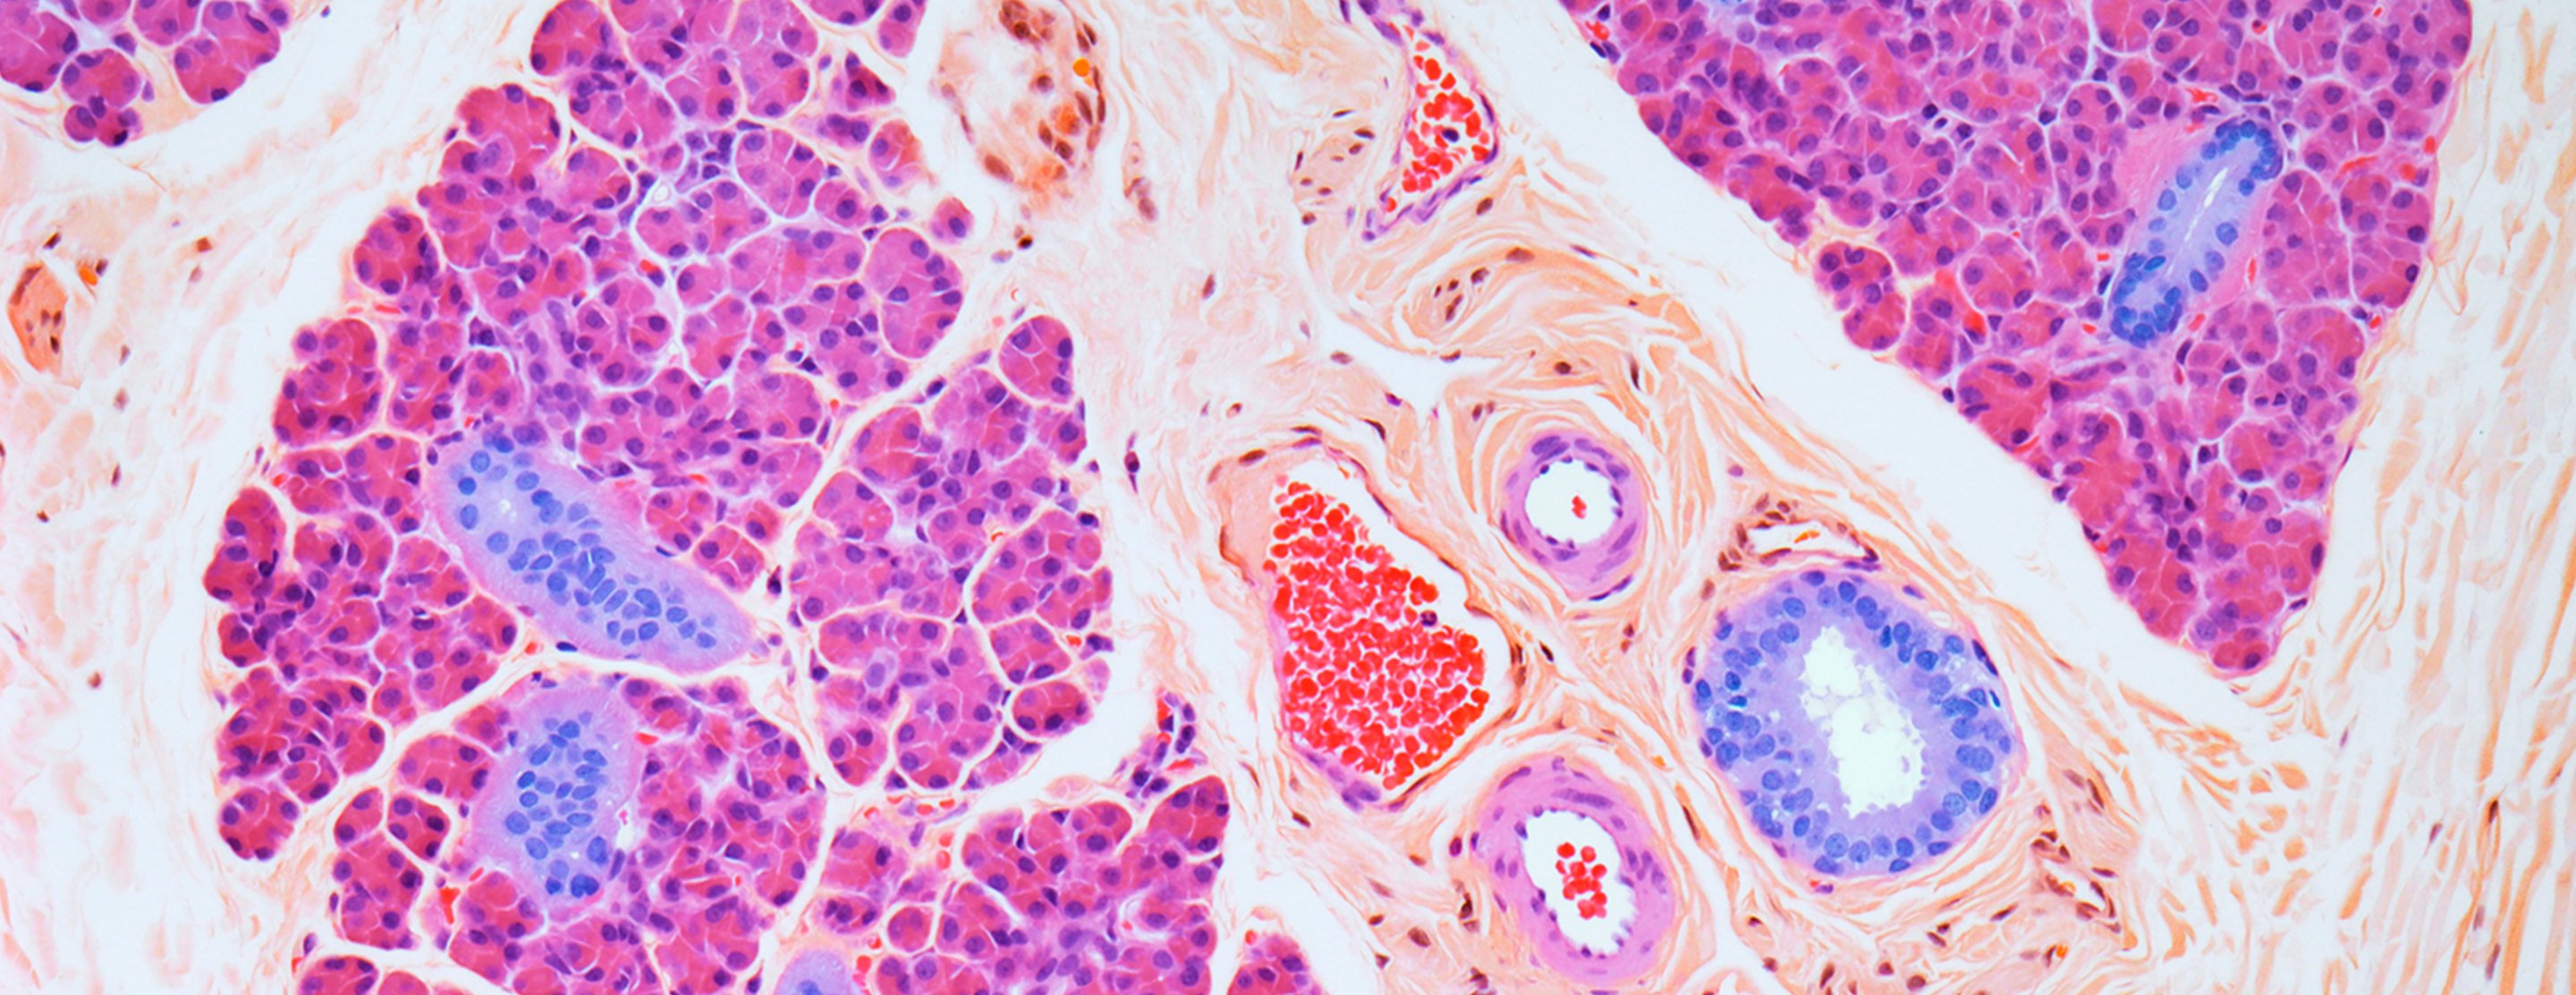

The salivary glands are located on each side of the head, in the cheeks just in front of the ears, and under the jaw. They release saliva into the mouth.